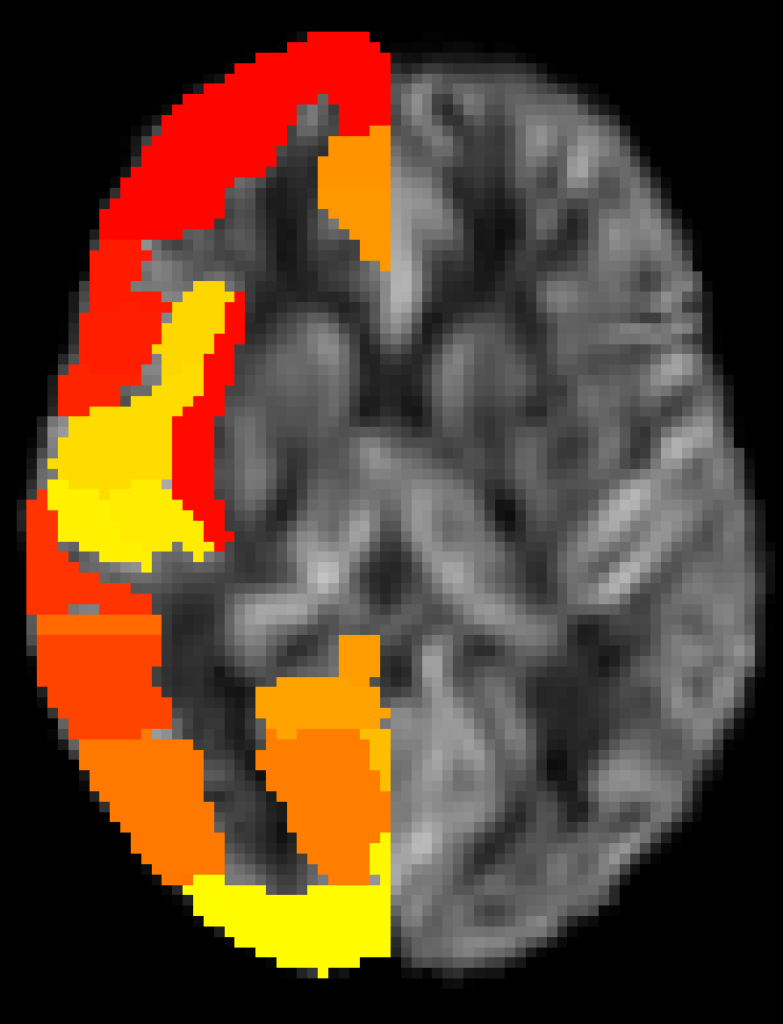

そして、最終的なゴールである「Harvard-Oxfordアトラスへの重ね合わせとROI解析を行った結果がこちらです。 無事にCSV形式で各領域の定量値を算出することができました。

ご覧の通り、Frontal Pole、Thalamus、Hippocampusなどの主要な部位において、概ね 30〜45 ml/100g/min 前後の値が得られています。

もし、10倍のゲインに気づかないままであれば、これらの値が「300〜400」という異常値になっていたはずです。 こうして生理学的に妥当な数値データとして出力されたのを見たとき、ようやく安心することができました。